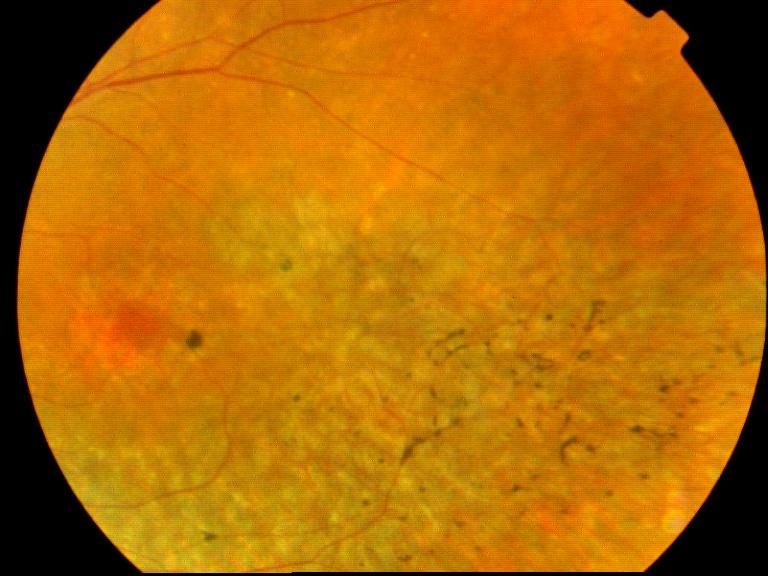

RETINOPATHIE PIGMENTAIRE